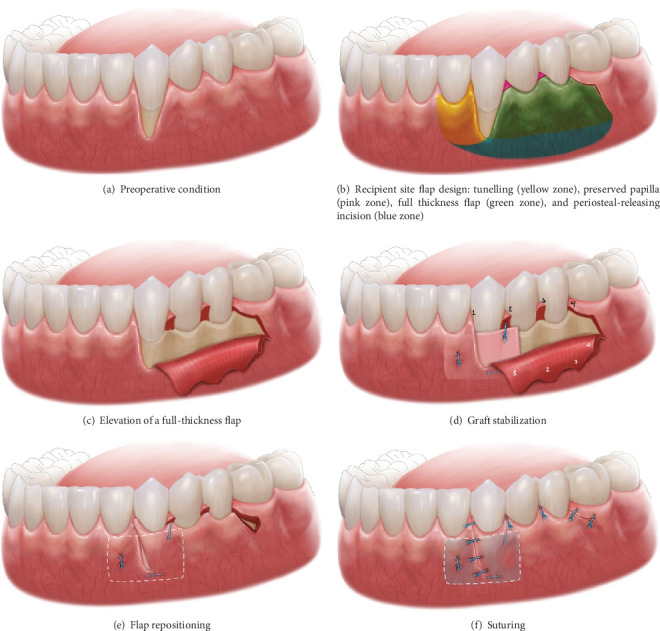

背景:目前已经提出了几种治疗牙龈萎缩的方法,并取得了积极的效果和临床可接受的结果。然而,大多数需要两阶段的手术,有一些缺点。本临床报告描述了改良的旋转皮瓣技术结合双成分释放切口和单侧隧道入路治疗牙龈退缩的治疗过程和临床结果。方法:32岁男性,非吸烟者,经正畸治疗后,33牙后退6mm, 43牙后退8mm。从硬腭取8 × 12 × 1.5 mm大小的结缔组织移植物。采用裂厚法在犬的内侧建立隧道皮瓣。在第二前磨牙的远端放置一个缩小的切口,包括一个弯曲的部分,遵循犬齿和前磨牙的颈椎轮廓,并以双部分释放切口结束。将移植物插入隧道,将牙龈瓣重新定位并固定以覆盖暴露的牙面。结果:随访6个月和1年,平均根管覆盖率100%,无疼痛和牙敏。结论:虽然需要进一步的研究和长期随访来评估该手术的有效性,但本病例报告表明,该技术不仅增加了根覆盖,而且仅在一次手术预约中就使粘膜宽度角化。

Background: Several techniques have been proposed to deal with gingival recession and gain positive effectiveness and clinically acceptable results. Nevertheless, most require a two-stage surgical procedure with several drawbacks. The present clinical report describes the treatment procedure and clinical outcomes of a modified rotated flap technique incorporating a double-component releasing incision and one-sided tunnel approach for the management of gingival recession. Methods: A 32-year-old male nonsmoker presented with a recession of 6 mm at tooth 33 and 8 mm at tooth 43 after orthodontic treatment. An 8 × 12 × 1.5-mm-size connective tissue graft was harvested from the hard palate. A tunnel flap was created on the mesial side of the canine using split-thickness technique. A reduced incision was placed distal to the second premolar, consisting of a curved segment that followed the cervical contours of the canine and premolars, and concluded with a double-portion releasing incision. The graft was inserted into the tunnel, and the gingival flap was repositioned and secured to cover the exposed tooth surface. Results: After the 6-month and 1-year follow-ups, the mean root coverage rate was 100% without pain and tooth sensitivity. Conclusions: Although additional studies and long-term follow-up will be needed to evaluate the effectiveness of this procedure, this case report showed that this technique not only increases root coverage but also keratinized the mucosa width in only one surgical appointment.